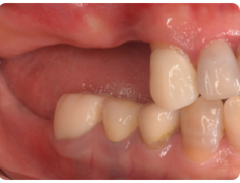

歯周病が進行し、グラグラして物が嚙めず、抜歯してインプラントにしていくことに。

インプラントはストローマンを使用、上部構造はジルコニアセラミックス